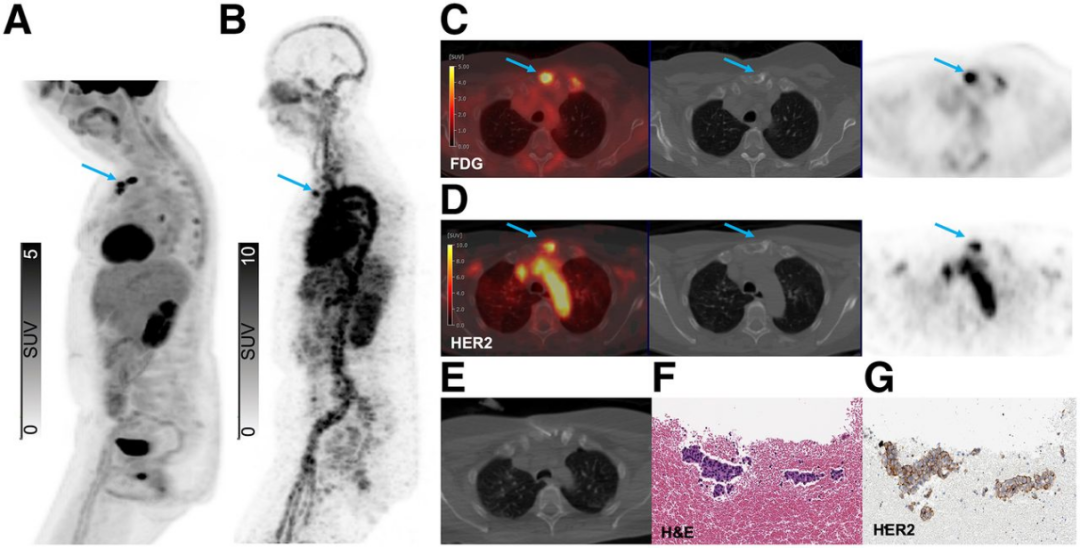

来自89Zr-ss-帕妥珠单抗队列的代表性患者展示了HER2表达的全谱系分布,图2-4展示了不同病例的HER2 PET图像和相应的病理结果。图2显示了一个HER2阳性胸骨病灶,图3显示了同一患者体内的HER2-0和HER2低表达骨病灶,图4显示了一个HER2-0肝脏病灶。

图2. 一例患者HER2 PET成像显示的HER2阳性胸骨病灶